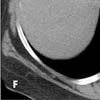

A CT image below the level of the heart (E) shows extensive venous collaterals that extend to the inferior vena cava (arrows). Venous collaterals extending to the inferior vena cava are also evident on another slice in the upper abdomen (F, arrows).

Figure E

Figure F